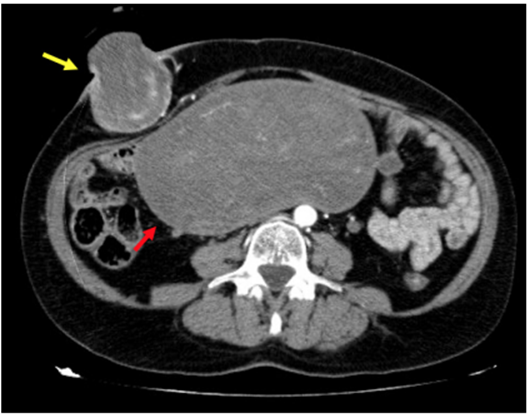

Paciente mujer de 59 años, sin antecedentes médico-quirúrgicos de interés, que consulta al servicio de Urgencias por lesión cutánea ulcerada, de crecimiento progresivo, en fosa ilíaca derecha. Se realizó ecografía abdominal y posteriormente tomografía computarizada (TC) abdominopélvica donde se identificó una masa uterina sugestiva de mioma gigante (180x86x177 mm), muy probablemente malignizado a sarcoma, y una masa subcutánea, sugestiva de metástasis parietal, sin signos de sangrado activo, y sin otros signos de diseminación a distancia (Figura 1). Ante estos hallazgos se decidió llevar a intervención quirúrgica urgente, realizándose resección en bloque de la lesión subcutánea de fosa ilíaca derecha (Figura 2). El estudio anatomopatológico diagnosticó una metástasis de sarcoma del estroma endometrial de alto grado. Se remitió al Comité de Tumores Ginecológicos para completar tratamiento con histerectomía + doble anexectomía + citología de líquido peritoneal en forma programada, por el Servicio de Ginecología y Obstetricia. La paciente recibió tratamiento adyuvante (quimioterapia y radioterapia) con respuesta completa y supervivencia libre de enfermedad en el seguimiento hasta la fecha.